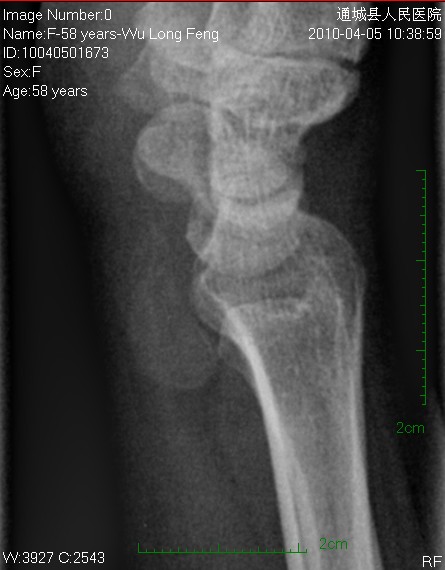

后三张是透视转动下点片放大。

平片见桡前软组织内一密度增高、边缘光整块影

片含诸构成骨无明显骨质破坏,软组织稍肿胀。片示软组织内异常密度影个人考虑为纤维组织增生,伴局部皮肤呈癣样变。考虑:银屑病性关节炎。建议作进一步检查。

我考虑腱鞘囊肿可能性大。另尺骨稍长,月骨、三角骨尺骨关节面密度减低。考虑尺骨撞击综合症